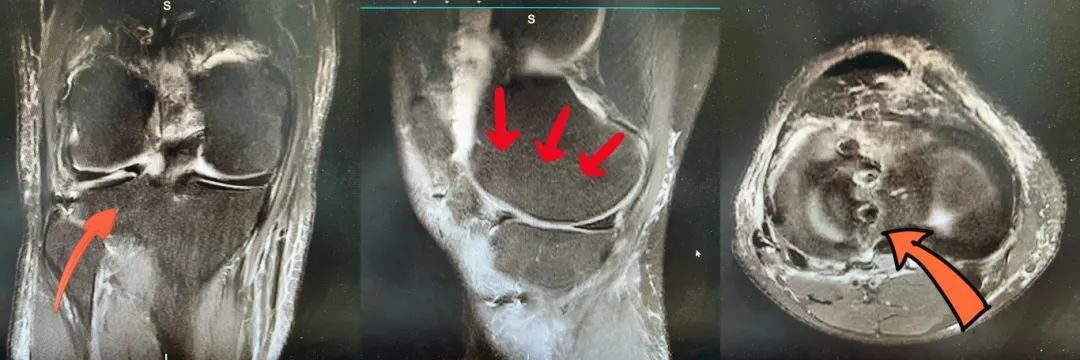

术后外侧半月板位置良好和股骨髁完全匹配

针对该患者病情,程飚团队采用MRI等影像技术对患者的膝关节进行详细评估,确认半月板的损伤程度和缺损区域。鉴于患者的年龄、活动水平及半月板损伤的严重性,决定进行半月板移植手术,以最大程度地还原关节结构和功能。完成一系列准备工作后,于近期为新疆小伙进行了关节镜下同种异体半月板移植术。手术非常成功,术后第二天患者即佩戴支具下地自主活动,并由科室康复团队开展术后康复锻炼。